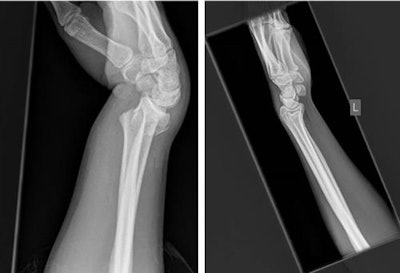

The authors carried out an extension to a previous study in which radiographs were preprocessed using a semiautomated cropping process. The aim was to improve the accuracy of the network by removing unnecessary parts of the image. These radiographs were then used to retrain the Inception v3 network using the transfer-learning process.

A total of 11,112 lateral wrist radiographs produced at the Royal Devon and Exeter Hospital in Exeter between 1 January 2015 and 1 January 2016 were used to retrain the Inception v3 network after an eightfold amplification of the original images. To reduce overfitting, an automated technique was used to identify the anatomical region of interest and crop the non-necessary image portions -- a process termed region of interest focusing. Given the large sample size, automation of the process was necessary for feasibility, according to Thurston and colleagues.

The Inception v3 network was then retrained using the region-of-interest focused radiographs. The model output was designed to produce a continuous value of between 0 and 1, with higher values indicating a fracture. A set of 50 "fracture" and 50 "no fracture" radiographs were used in final testing of the model.

Automated region-of-interest focusing was able to crop the image appropriately in 92.4% of cases, reported Thurston, who has a special interest in musculoskeletal radiology, open learning initiatives, and open-source software. The remainder of the cases were cropped manually.

The accuracy of the model was improved when the region-of-interest focusing was applied reaching an area under the curve (AUC) of 0.978, compared with an AUC of 0.954 without region of interest focusing.

The output of the network was a continuous score from 0 to 1. By setting the cutoff for fracture diagnosis at > 0.4, the team achieved a sensitivity and specificity of 96% and 94% respectively.